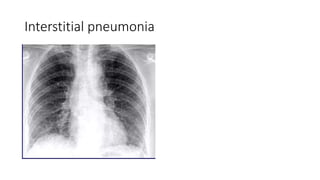

Interstitial pneumonia

• Interstitial pneumonia(inflammatory inflitrate of alveolar wall)